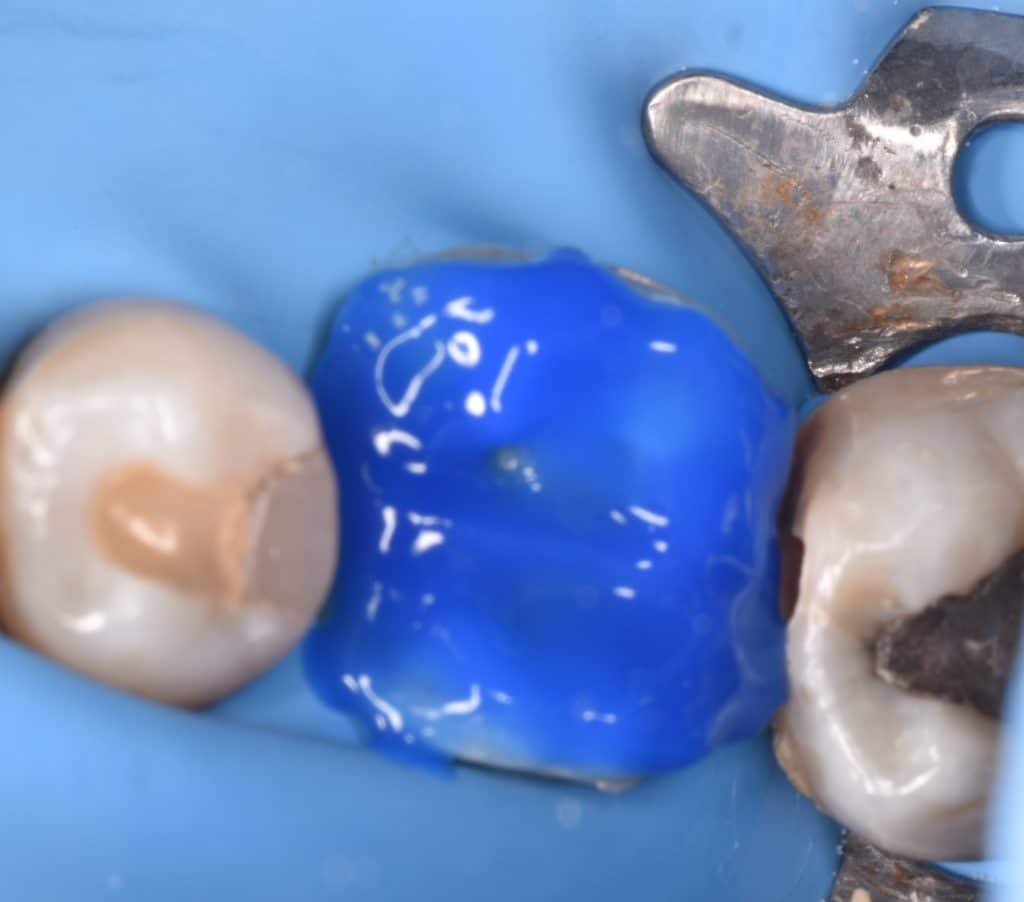

Tooth prepared to cementation by :

1_Isolation

2_sandblasting

3_phosphoric acid 37% and rinse

4_ bond application without curing

Put the cement materail and go for cementation

Immedait after cementation